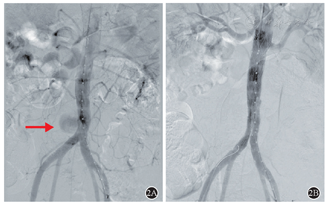

患者,男,51岁,因"反复双下肢水肿7月,右下肢肿胀加重3 d"为主诉入院。患者7月前无明显诱因出现双下肢肿胀,右侧较重,活动及久站后加重,晨起消失。无间歇性跛行及下肢疼痛,未诉腹部及背部疼痛病史。患者至医院行下肢深静脉彩超检查诊断为下肢静脉曲张并给予治疗后,患者症状反复。3 d前患者因"右下肢肿胀加重"至我院就诊。查体:右下肢肿胀,伴小腿胫前色素沉着,范围约6 cm×4 cm。彩超提示:右侧髂总静脉、髂外静脉、股总静脉上段血栓形成,腹主动脉瘤合并血栓形成。上腹部增强CT可见:腹主动脉下段局部管壁见小破口出血,周围组织包裹,血肿形成(图1A),下腔静脉、右侧髂总静脉、髂外静脉及股静脉上段可见充盈缺损影(图1B)。冠状位重建图像(图1C)显示腹主动脉的假性动脉瘤压迫下腔静脉,导致下腔静脉狭窄(图2A)。诊断明确后,行腹主动脉瘤腔内隔绝术(图2),术后3 d拟定行"下腔静脉造影并下肢静脉血栓清除术",术中造影可见下腔静脉下段闭塞,大量侧支循环形成(图3),开通困难。遂术后予以利伐沙班20 mg QD抗凝治疗。

1A:腹主动脉下段局部管壁见小破口出血,周围组织包裹,血肿形成;1B:右侧髂总静脉、髂外静脉及股静脉上段可见充盈缺损影;1C:冠状位重建图像显示腹主动脉近髂动脉分叉处假性动脉瘤(52 mm×43 mm)压迫下腔静脉,导致下腔静脉闭塞。